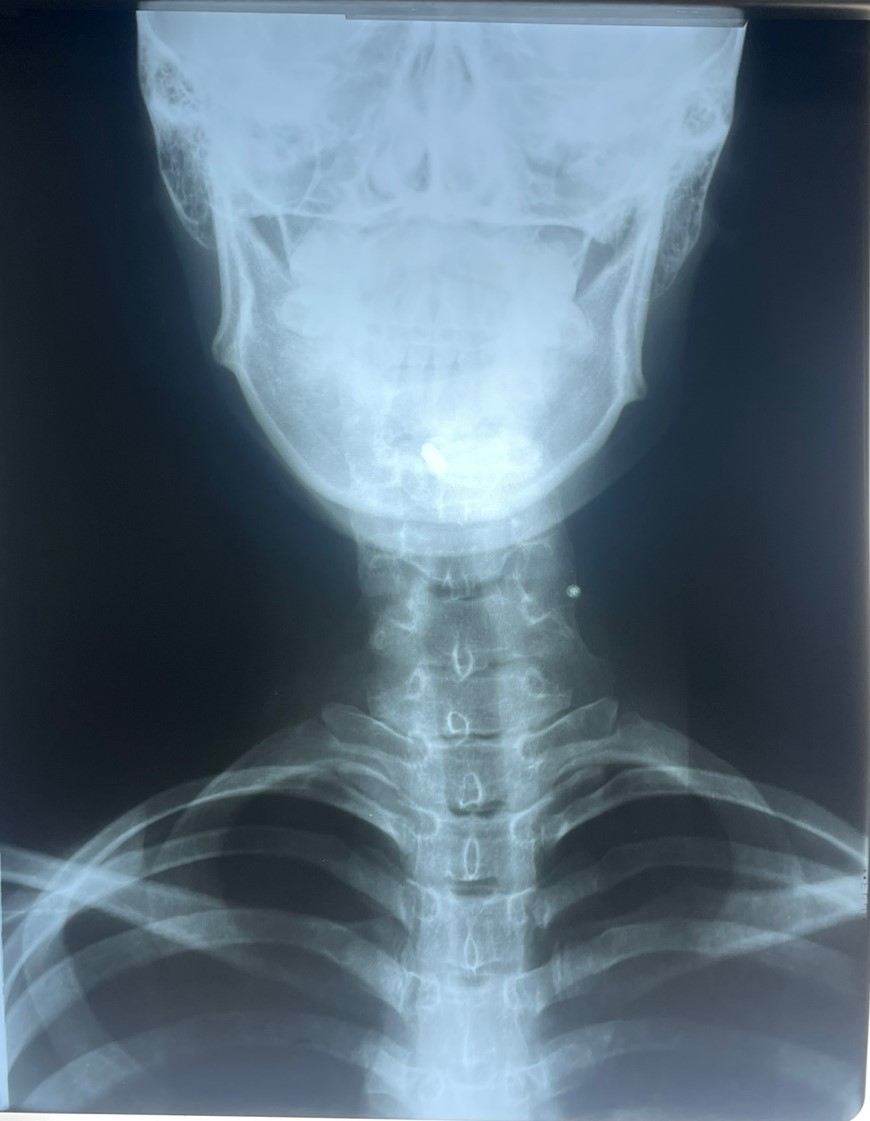

사경증, 근긴장이상증은 왜 오는 것일까? 이유는 간단합니다. 경추가 휘어져서 그런 것입니다. 환자들이 증상에 놀라서 대학병원을 가면 사경증이라는 진단명을 처음 들어봅니다. 목이 떨리고 목이 기울고 하기 때문에 어떻게 해야 할지 환자가 놀라고 사실 의사도 당황스럽기는 마찬가지입니다. 약물을 강하게 쓰다가 부작용을 심하게 겪는 경우도 있고 요즘은 보톡스로 치료를 하기도 하는데 저희 한의원에서는 CBA를 이용한 경추교정을 합니다. 경추가 심한 역커브를 가지고 있으면서 옆으로도 휘게 되면 환자는 목이 많이 당기고 뻐근함을 느끼게 되고 심하면 이제 목이 돌아가고 연축까지 하게 됩니다. 이러한 것은 경추가 하나가 빠져 있기 때문에 목 주변을 잘 흘러야 하는 신경을 눌렀다 조였다 하는 결과가 생겨서 그렇다고 봅니다. 무엇인가 특별한 것이 원인이 되어서 그것 때문에 그렇다 할 수 없다는 것입니다. 허리 디스크는 왜 생기는 것입니까? 허리 간격이 좁아져서 그런데 허리 간격은 왜 좁아집니까? 지구에 중력이 있고 사람은 직립을 하고 목뼈는 하나가 빠져있고 하니까 몸속에서 척추는 주저앉고 휘어지게 되는데 굴곡이 있는 부위에서 디스크가 잘 빠지는 것입니다. 그래서 사람은 허리가 아프게 마련이고 그런 척추의 변형 중에 하나가 측만증이고 목의 1,2,3번이 극단적으로 휘게 되면 외관상으로 목이 기울고 돌아가고 연축을 합니다.

터커리한의원에서 중점 치료를 하는 CBA를 이용한 턱관절 음양자세 교정술은 경추교정에서 끝나는 것이 아니라 CBA스프린트로 교정된 경추 1,2번을 턱관절과 고정을 해준다는 것이 또한 큰 치료의 핵심입니다. CBA스트린 트는 1시간 정도 착용하고 있으면 일자목부터 역커브, 휘어진 목, 좁아진 디스크 간격을 모두 바른 S라인으로 이동, 수술을 시켜줍니다. 경추와 척추 뼈의 문제로 생긴 통증과 이상증을 척추를 직접 물리적인 치료를 하여 몸속에 있는 척추에 정상적인 힘을 가해준다는 것입니다. 그러니 효과가 좋을 수밖에 없고 사경증도 결국엔 휘어있고 역커브가 있는 정도로 인식이 되어서 사경증 치료가 되고 난 후에 다시 X-ray를 찍어보면 목뼈가 바르게 교정된 것을 확인할 수가 있습니다. 사경증은 측만증과 같다고 봅니다. 목이 휘고 등이 휘어있다면 휘어있는 목과 등을 바르게 하는 CBA교정을 터커리한의원에서 지금 받아야 합니다. 치료 기간은 많이 휘어 있으면 오래 걸리고 조금 휘어 있으면 조금 오래 걸립니다. 치료는 제가 해드리지만 기간까지는 알 수 없습니다. 쉽게 생각하고 오시면 안 됩니다. 반드시 오시기 전에는 X-ray 그림을 지참하시고 오시기 바랍니다.https://naver.me/FgiE6Sux